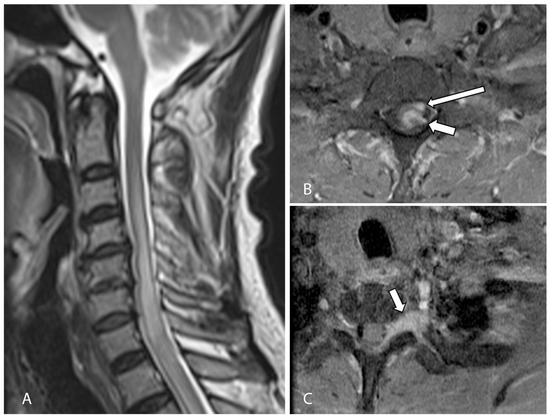

Post-operative recovery was unremarkable, and adjuvant radiation therapy was started 1 month after surgery. The patient received a total of 33 sessions of radiotherapy over the following 2 months. However, he developed worsening left-sided weakness and new left-sided facial pain within these 2 months. A follow-up MRI spine at 10 weeks post resection demonstrated an enlarging enhancing tumor in the left spinal cord at the levels of C7 and T1 and along the left T1/2 neural foramina. In addition, there were new enhancing lesions along the brainstem and pons, most prominent at the origin of the left trigeminal nerve trunk (Figure 4). Gamma knife surgery was performed for this lesion to reduce the left-sided facial pain.

Figure 4.

T1-weighted, fat-suppressed, contrast-enhanced axial (A) and sagittal (B) images from a follow-up MRI cervical spine showing a large enhancing lesion (arrows in (A,B)) consistent with local recurrence at the levels of C7 and T1, involving the spinal cord and left neural foramen. (C,D) T1-weighted, contrast-enhanced axial MRI of the brain showed new enhancing lesions at the anterior pons (arrow in (C)) and at the left anterolateral surface of the pons (arrow in (D)) involving the left trigeminal nerve, which accounted for the new left-sided facial pain.